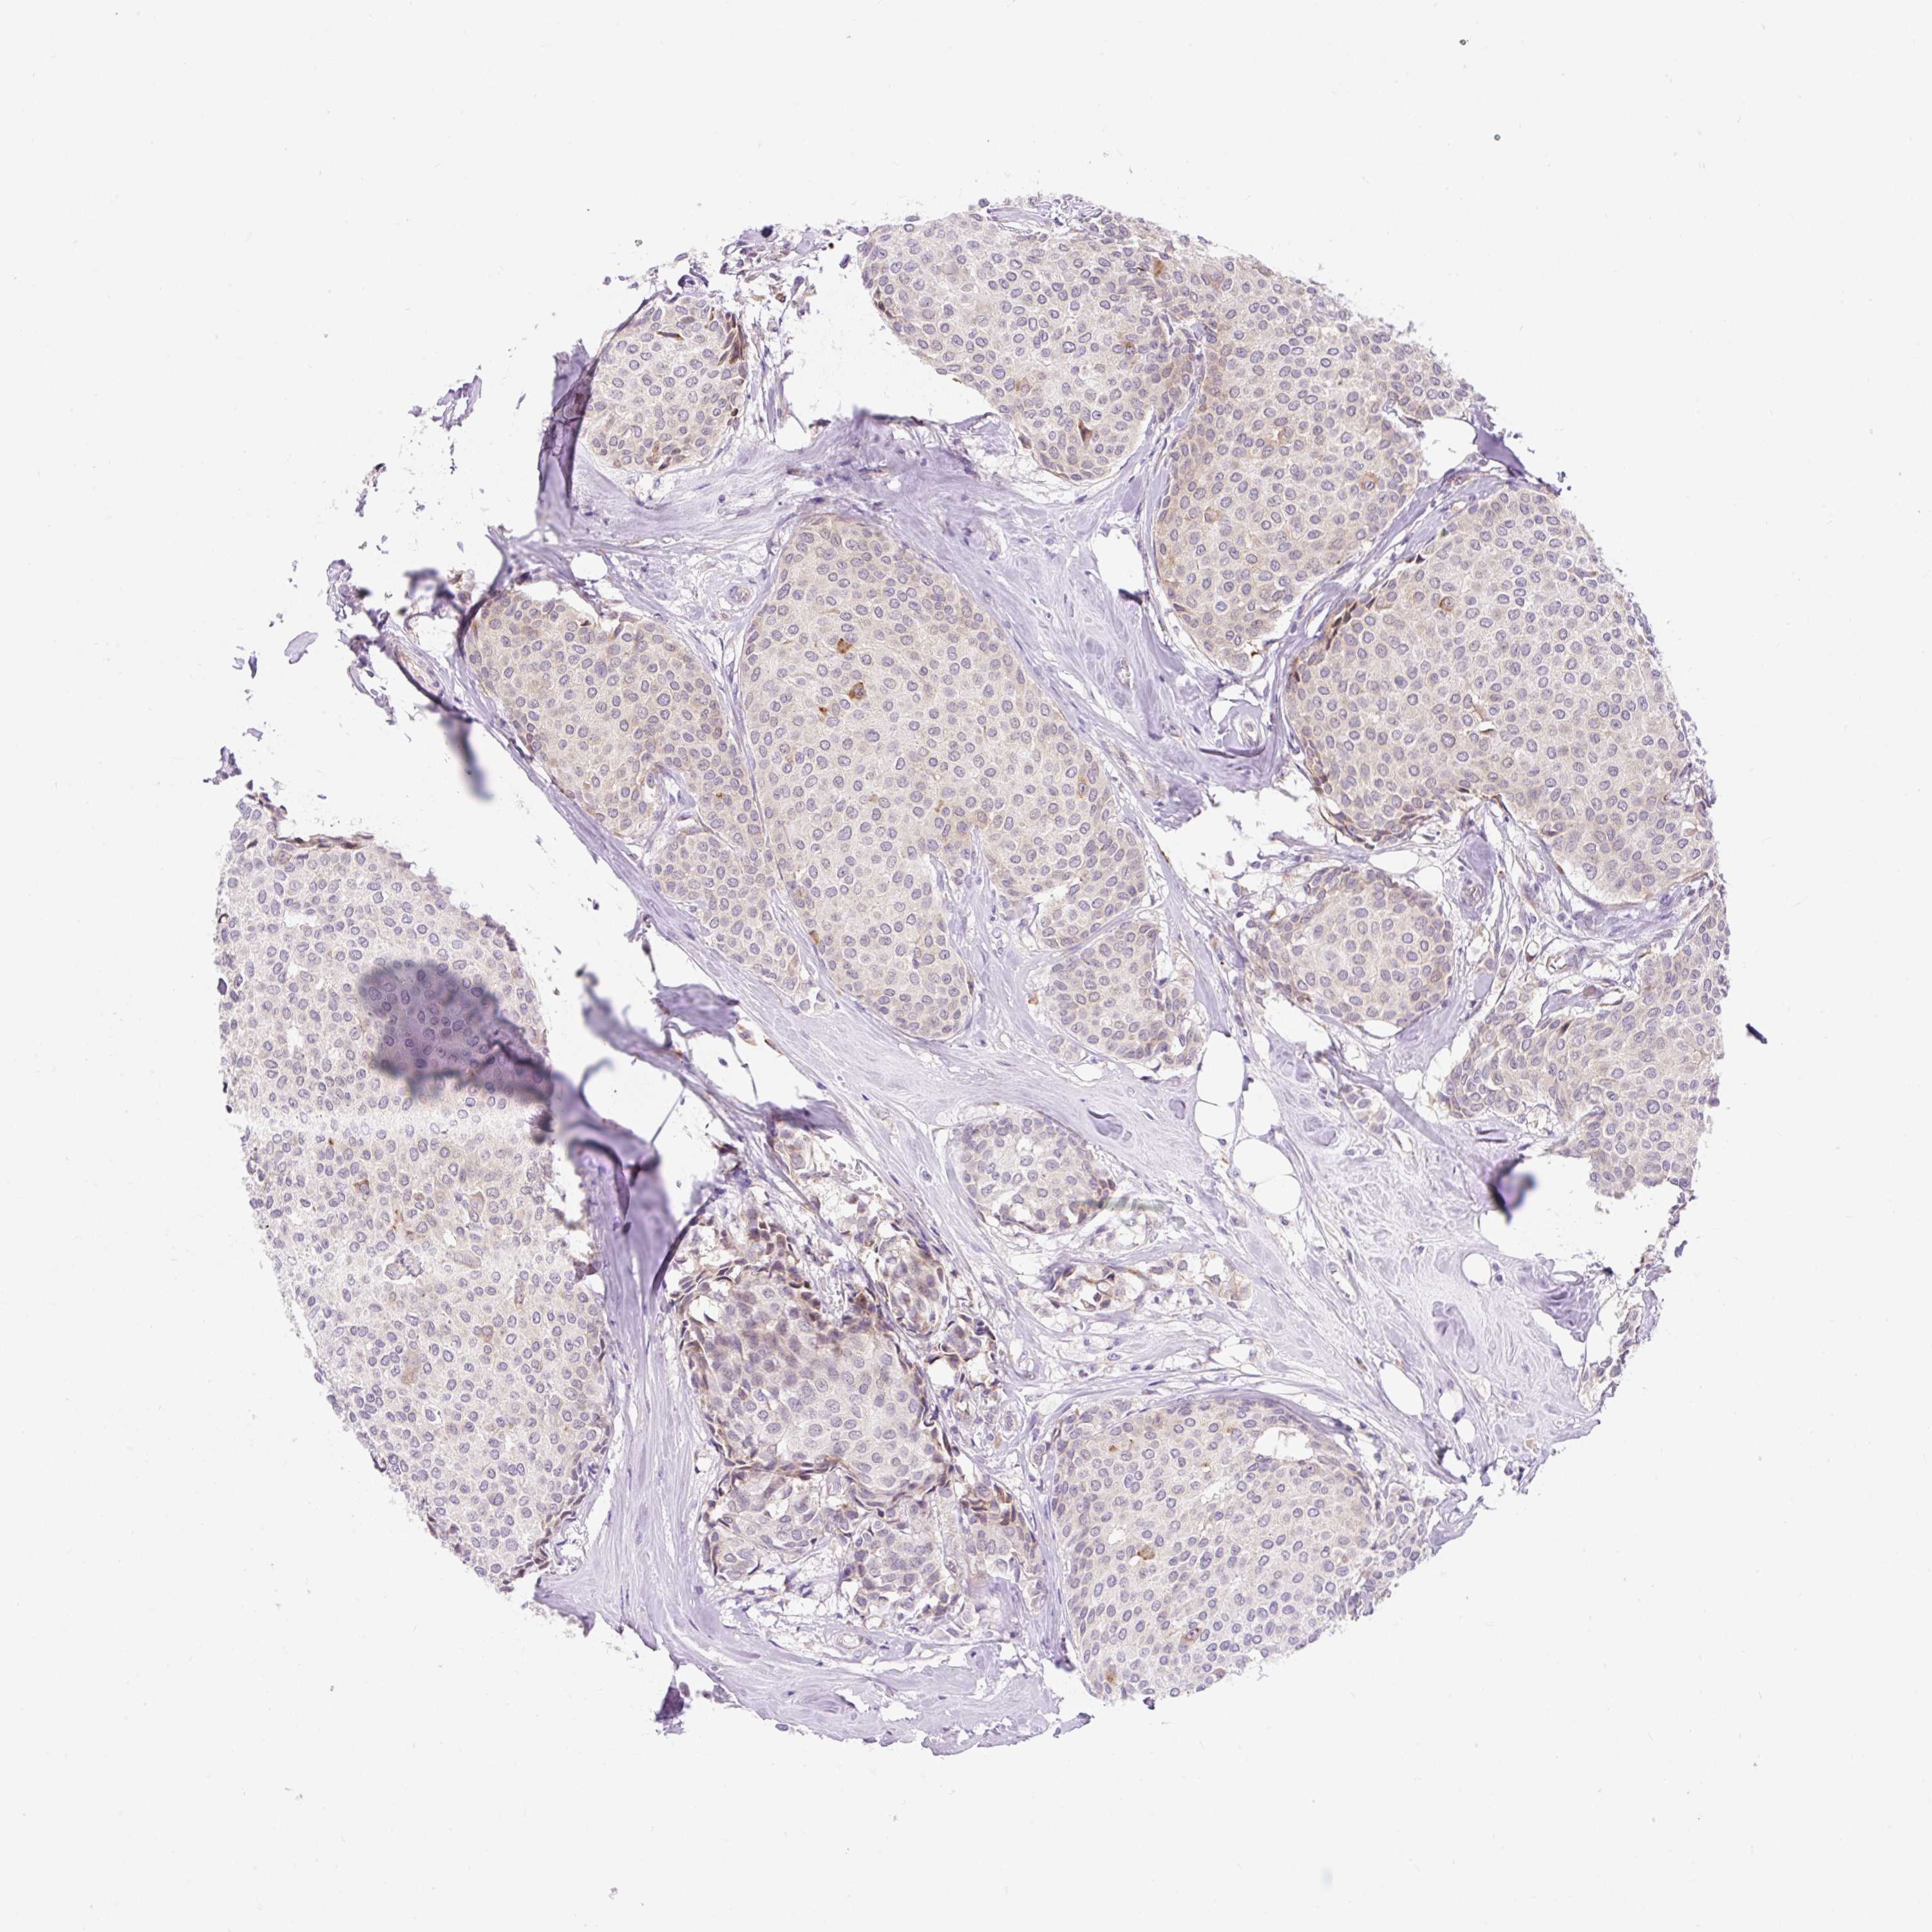

CANCER BREAST CANCER Show tissue menu

BRCA TCGA BRCA VALIDATION PROTEIN EXPRESSION

ANTIBODIES

AND

VALIDATION